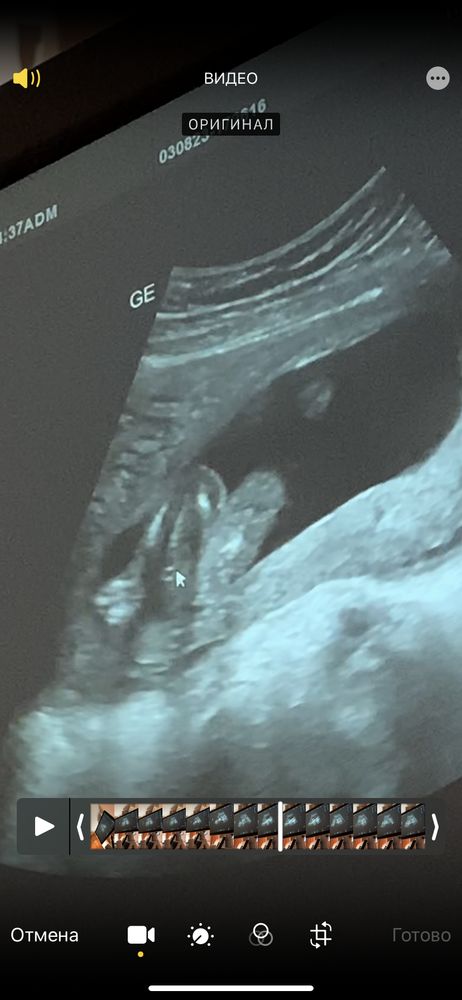

Пол ребёнка

Девочка

Мне кажется, что девочка)

Это в 19 недель узи? Если да , то , мальчик

Аня Фомич, в 16 недель

Аня Фомич, похоже на девочку но врач не уверенна, жду 2 скрининг для подтверждения

Девочка или мальчик? 🤔😊 Мальчик или девочка?